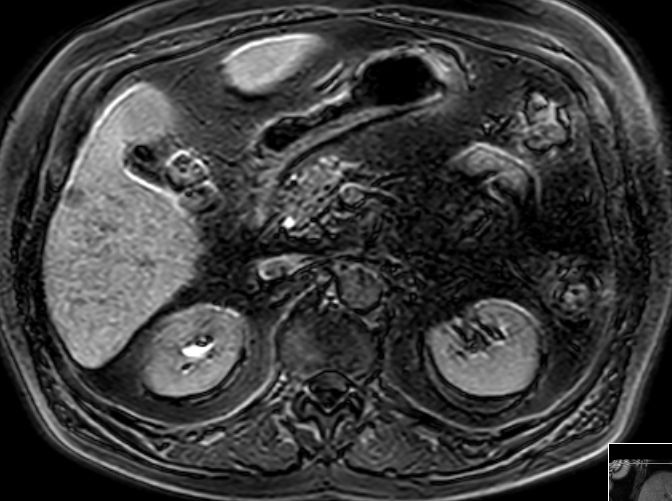

Herd im Segment 4a unmittelbar am Gallenblasenbett 48mm.

![]() | |

Im 5. Segment subkapsulär rechts lateral ein 11mm großer, signalabgesenkter Leberherd.![]() |